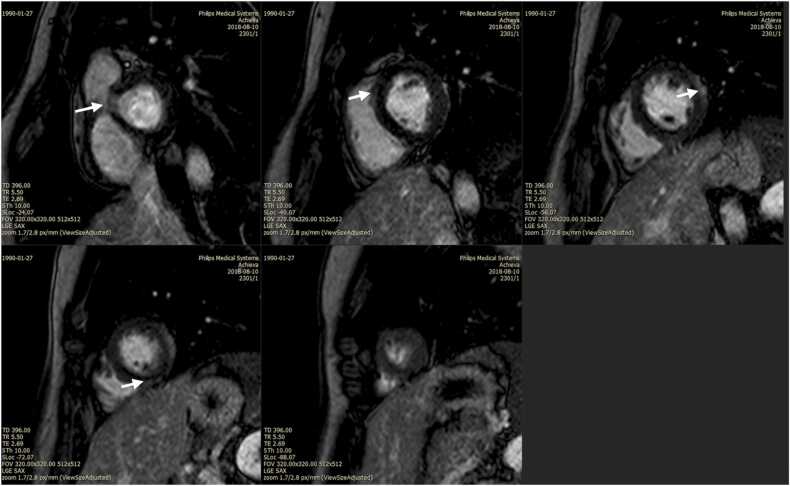

The vital sign on the first-day admission was slight tachycardia (104 bpm), the general examination was unremarkable. The patient underwent several laboratory and imaging workups upon admission. Chest radiograph was within normal limit, electrocardiography (ECG) showed small q wave in II, III, aVF, and V4-V6 and t wave flattening in II, III, aVF. The laboratory result showed that hematologic study and CRP level was within normal limit. There were elevated liver function test (AST 114 U/l, ALT 112 U/l), elevated LDH (518 U/l), elevated high sensitivity troponin T (571 ng/ml), elevated NT pro BNP (88 pg/ml). Evaluation of common infectious causes such as dengue, typhoid fever, and malaria came out negative. The patient was diagnosed with acute myocarditis and received methylprednisolone 72 mg/day, lansoprazole 30 mg b.i.d., bisoprolol 10 mg per day, ramipril 10 mg per day. On the third day of admission, the chest pain was improved, and electrocardiography was performed and showed no significant anatomical and functional abnormality. Chest X-ray showed no sign of cardiomegaly. Cardiac MRI showed Late Gadolinium Enhancement (LGE) areas consistent with myocardial necrosis, depicting transmural and subepicardial involvement at the basal anteroseptal segment, as well as midwall, subepicardial involvement at the mid anterolateral, and inferior segment. (Fig. 1). Laboratory workup was reperformed on the sixth-day admission and was within normal limit. The patient was then discharged with a tapering dose of methylprednisolone, lansoprazole, bisoprolol, and ramipril, and with several education materials such as bed rest and activity limitation for six weeks, echocardiography, and MRI reevaluation in 3 months.

Fig. 1.

Cardiac MRI showed myocardial necrosis in multiple sites (white arrows).